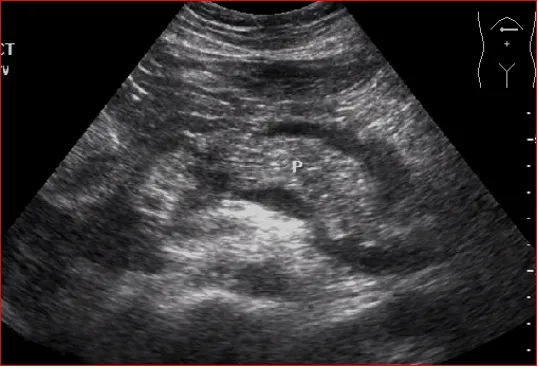

巨大胰腺假性囊肿压迫胰腺实质